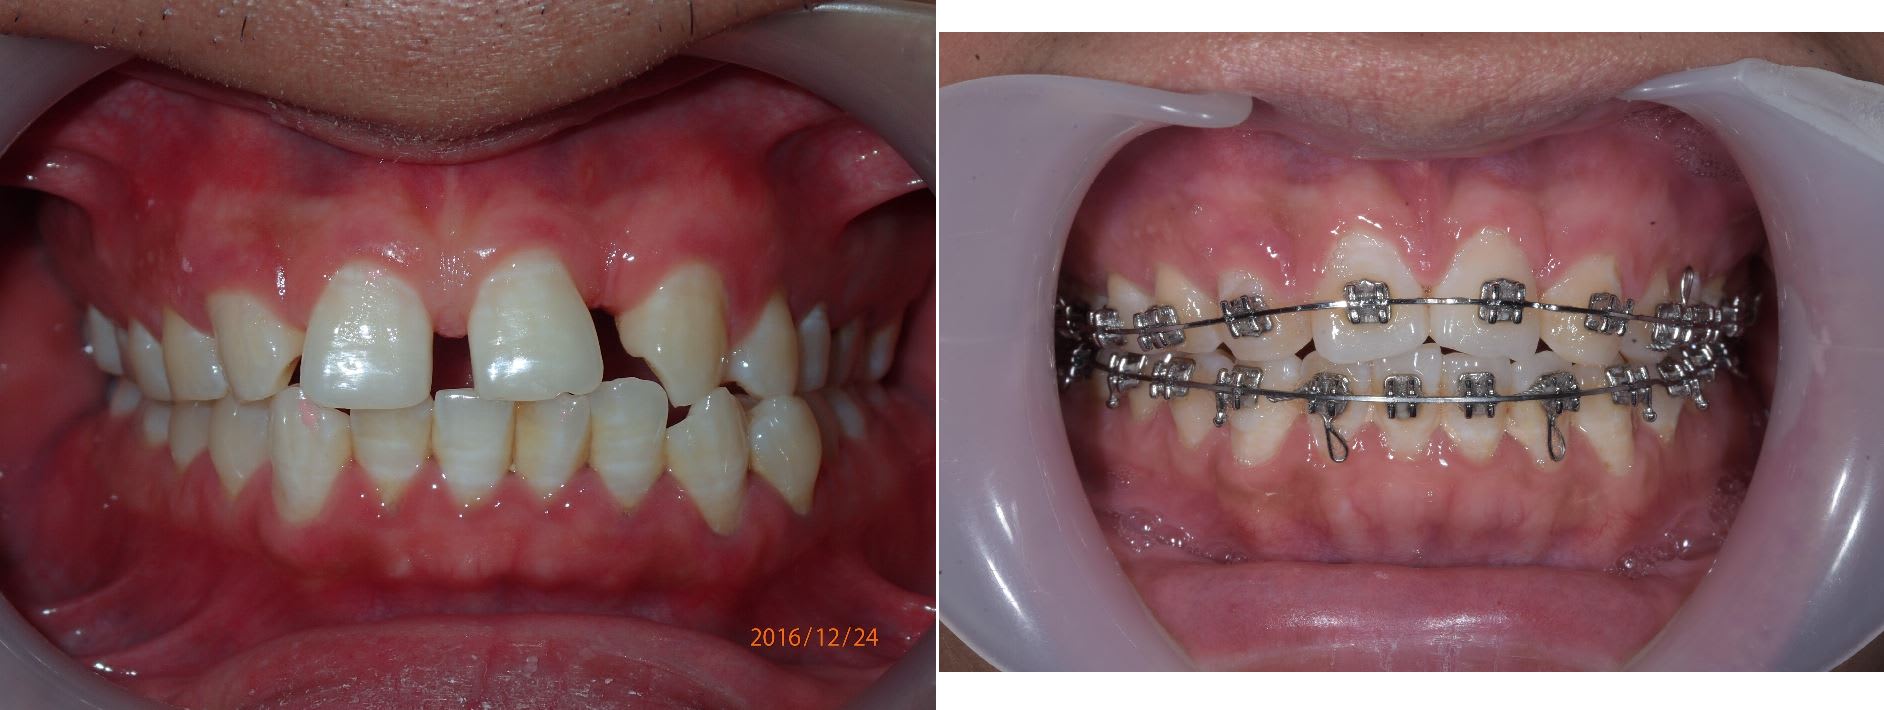

Un cas de double agénésie , 12 et 22 avec une class III et déviation de la mandibule.

1 ans et 2 mois de traitement pour l'instant. C'est pas encore parfait mais la correction sagital est presque terminé.

Juste pour dire que le fait d'être class II, I ou III n'est pas une contre indication dans le traitement ODF des agnésie.

PS : pas de minivisse utlisé pour ce cas, 100% bracket, file et élastique.